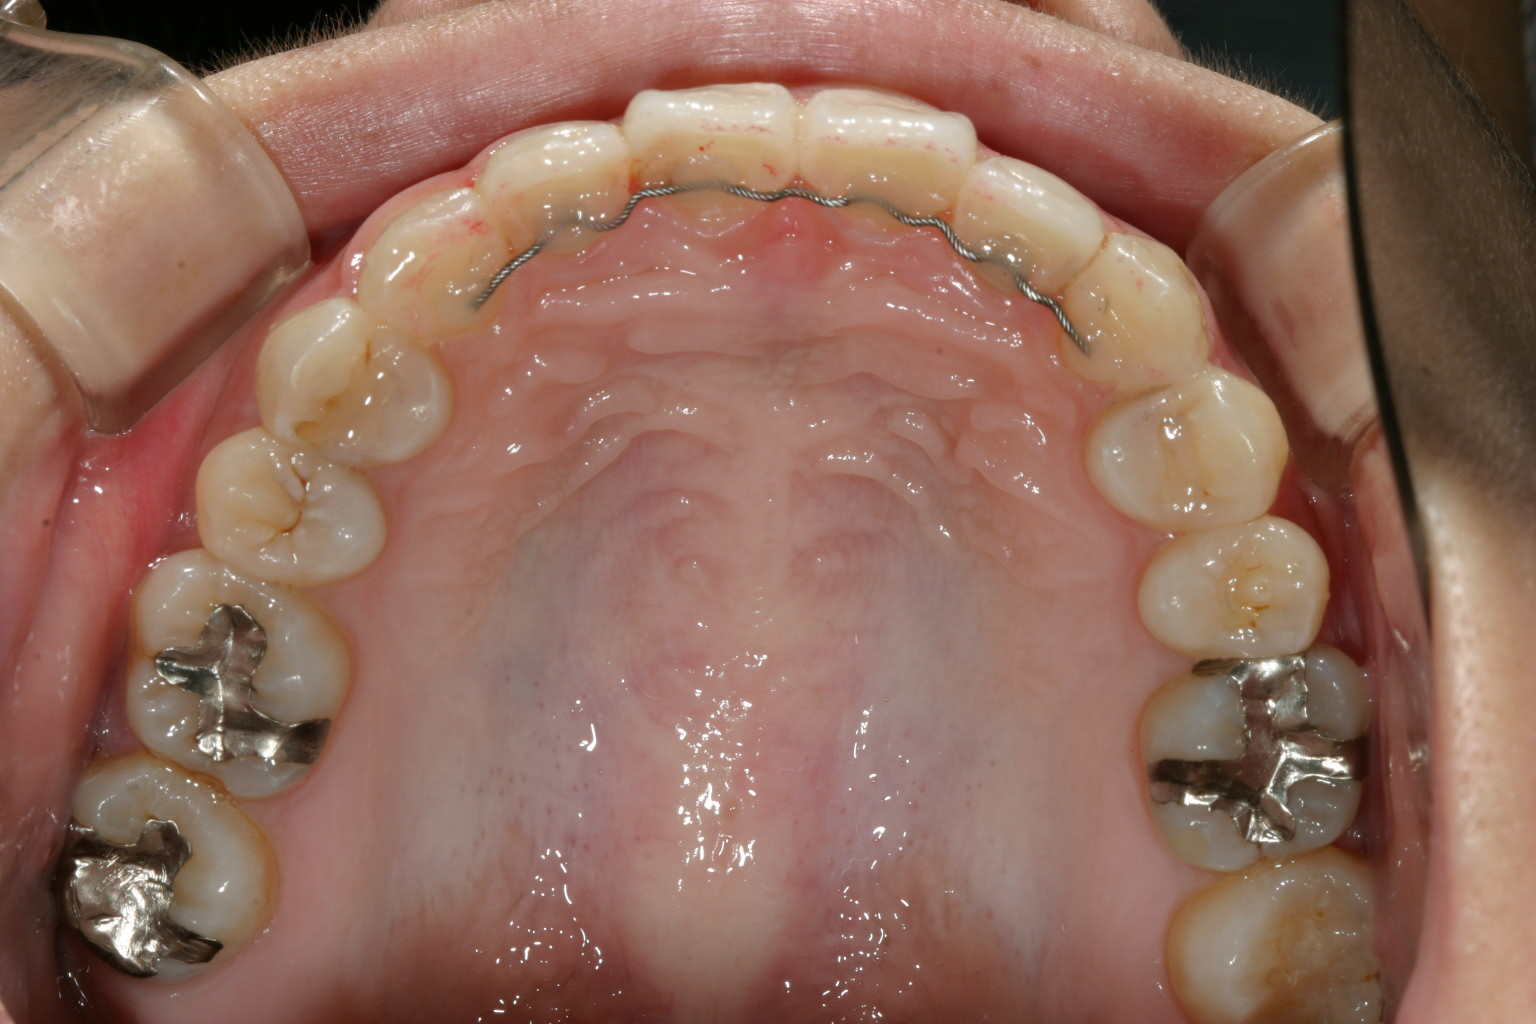

前歯かなり捻転してますね~

下の歯並びは矯正治療終わったかのように綺麗ですね~